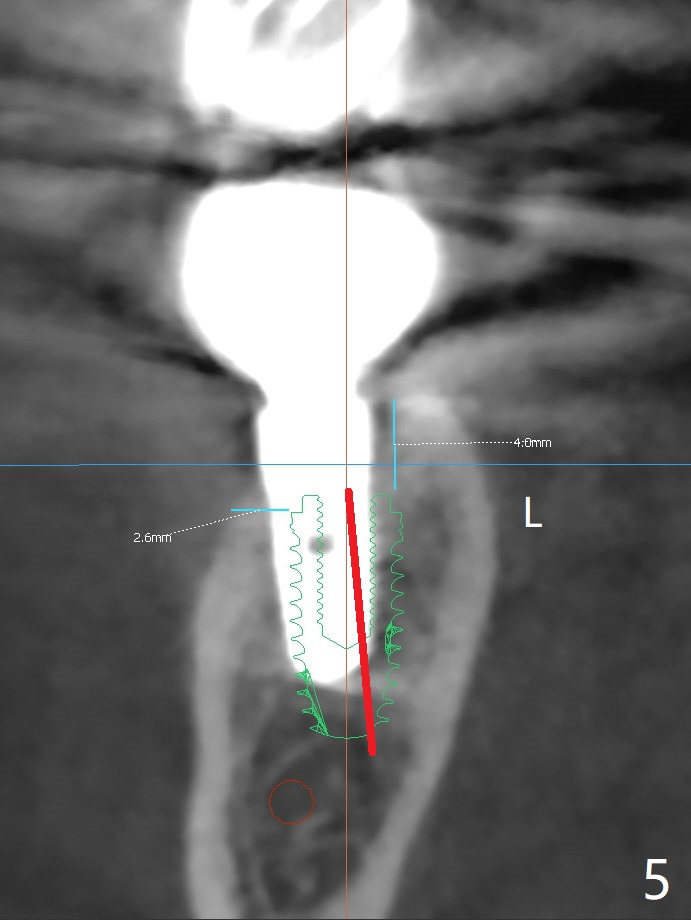

A 5x12 mm SM implant with periimplantitis at #30 is removed with a 5/6 mm trephine bur, small elevator and implant driver. A 3.8 mm Magic drill is used to start a new osteotomy in the lingual wall of the old one free hand. With the final drill (4.8x13 mm), a 5x11(3) mm Magicore is placed (Fig.1-4). The large buccal gap (Fig.2 arrowheads) is filled with allograft (Fig.3 *). The latter is covered by PRF, followed by suture. Periodontal dressing is applied around the 4.2x3 mm solid abutment and the coronal portion of the Magicore (Fig.4 <). The green outline in Fig.5 (CT coronal section) represents a new 5x10 mm implant (design), while the thick red line is approximately the long axis of the new implant. The implant heals in spite of buccal recession. Impression is taken with placement of a 4.3x5 mm solid abutment 4.5 months postop (Fig.6). Take follow-up CT to determine buccal bone formation.